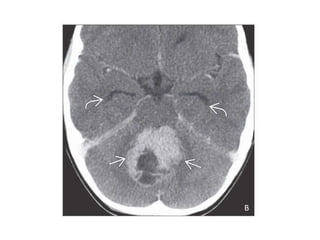

Left: axial NECT shows a poorly demarcated, infiltrative, mildly hyperdense

mass centered in pineal region with peripheral Ca++. There is invasion of

adjacent brain parenchyma & compressionof aqueduct of sylvius & resultant

hydrocephalus.Right: axial DWI MR shows restricted diffusion in solid mass &

better delineate the neoplasm & invasion of adjacent brain parenchyma.

Left: axial NECTshows a poorly demarcated, infiltrative, mildly hyperdense mass centered in pineal region with peripheral Ca++. There is invasion of adjacent brain parenchyma & compressionof aqueduct of sylvius & resultant hydrocephalus.Right: axial DWI MR shows restricted diffusion in solid mass & better delineate the neoplasm & invasion of adjacent brain parenchyma.